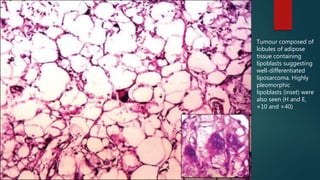

Tumour composed of

lobules of adipose

tissue containing

lipoblasts suggesting

well-differentiated

liposarcoma. Highly

pleomorphic

lipoblasts (inset) were

also seen (H and E,

×10 and ×40)

Tumour composed of lobulesof adipose tissue containing lipoblasts suggesting well-differentiated liposarcoma. Highly pleomorphic lipoblasts (inset) were also seen (H and E, ×10 and ×40)